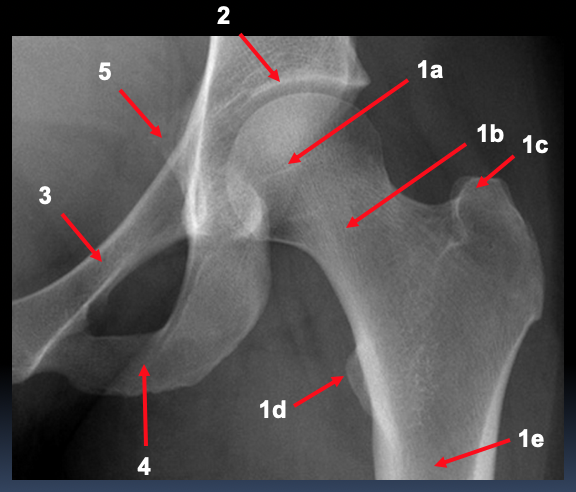

What is represented by 1 and 2 in the AP pelvic radiograph?

1. sacrum

a. ala

b. foraminae

2. sacroiliac joint

What is represented by 3 and 4 in the AP pelvic radiograph?

3. ilium

a. crest

b. ASIS

c. AIIS

4. ischium

a. spine

b. tuberosity

What is represented by 5 in the AP pelvic radiograph?

5. pubis

a. body

b. superior ramus

c. inferior ramus

d. symphysis

What is shown by 2, 3, 4 and 5 in this AP left hip radiofraph?